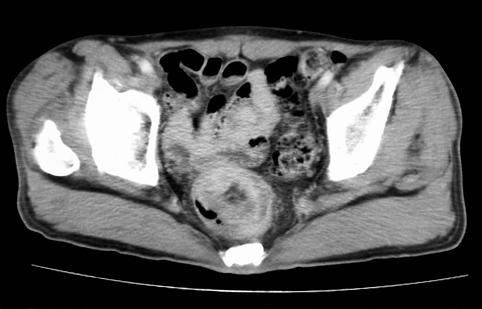

疾病(病理主体)的分类恶性上皮性肿瘤/粘液癌

部位(按器官分)大肠/直肠

检查方法CT

肿瘤的肉眼分类1型(肿瘤型)/

肿瘤最大直径40以上

肿瘤的深度mp